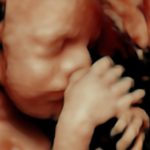

4D/5D/HD Ultrasound Gallery

Gallery